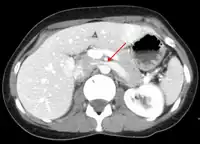

CT and MRI

CT and MRI can be used afterward to confirm compression by the AA and SMA with comprehensive measurements of the abdominal vasculature. A "beak sign" can often be seen in CT scans due to the LRV compression. However, CT and MRI cannot demonstrate the flow within the compressed vein. These two modalities can be used to confirm other evidence for NCS such as back-up of blood flow into the ovarian veins.[11][6]